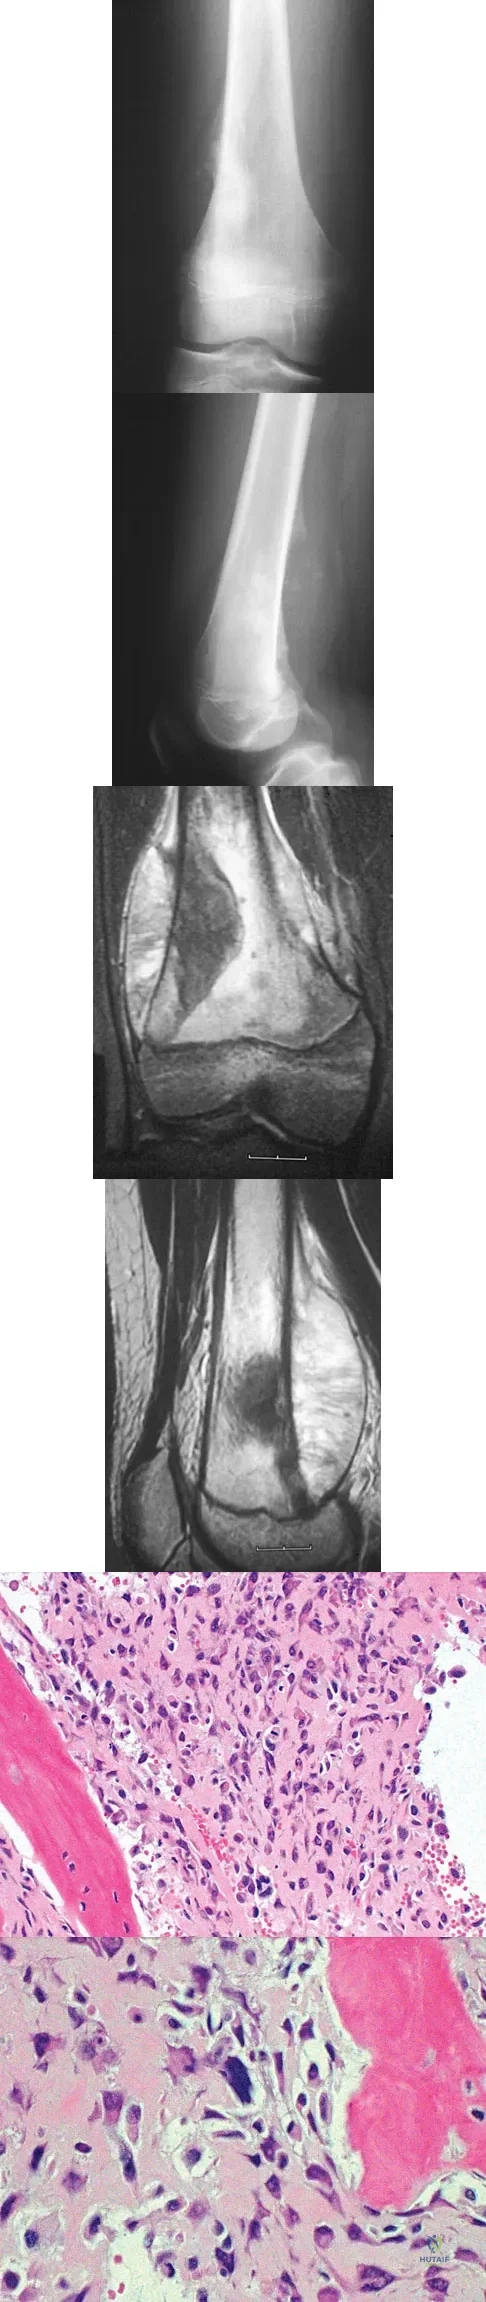

A 13-year-old boy has knee pain after sustaining a mild twisting injury while playing basketball 4 weeks ago. Radiographs and MRI scans are shown in Figures 24a through 24d, and biopsy specimens are shown in Figures 24e and 24f. Treatment should consist of

Explanation

An 18-year-old boy has had pain in the right knee for the past 6 months. Examination reveals some fullness behind the knee but no significant palpable soft-tissue mass. There is no effusion, and he has full knee range of motion. The remainder of the examination is unremarkable. A radiograph and MRI scans are shown in Figures 33a through 33c, and biopsy specimens are shown in Figures 33d and 33e. What is the most likely diagnosis?

Explanation